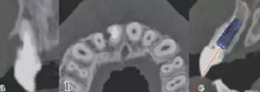

術(shù)前拍攝錐形束CT并做種植方案規(guī)劃。從圈紅處可以看出頰側(cè)骨組織不夠致密,建議備完孔后再做小翻瓣以觀察窩洞頸部的情況,圖2中的粉紅色及藍色HU值曲線顯示種植體內(nèi)部及其周圍的骨密度不高,為四類骨質(zhì),因此術(shù)中應(yīng)通過控制備孔的直徑或深度,以使種植體獲得較佳的初期穩(wěn)定性。

圖2 種植方案的規(guī)劃:a.頰舌側(cè)方向的截面圖,頰側(cè)圈紅處骨質(zhì)較疏松;b.近遠中方向截面圖;c.種植體周圍的骨密度